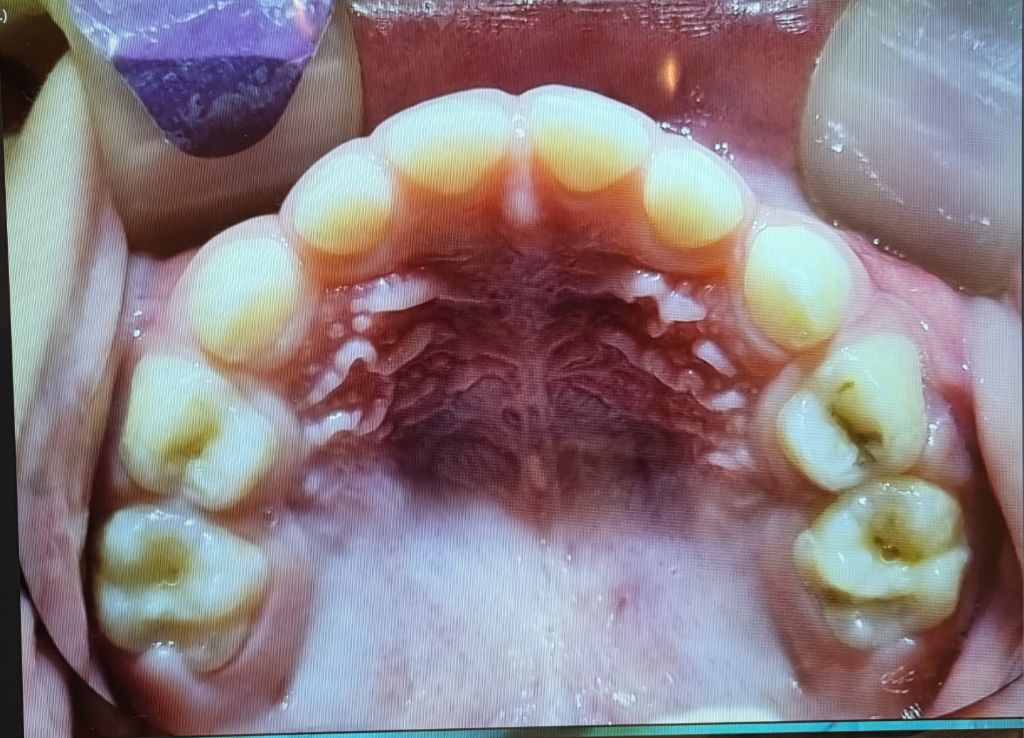

선생님 치과 방문도 계획했으나 전화문의 결과 너무 어려서 엑스레이 찍을 도구도 마땅치 않다는 안내에

일단 동네 어린이치과에서 엑스레이를 찍은 후 부탁해 사진을 받아 왔습니다.

이 치과에서는 모든 어금니에 충치가 다 있으나 (보는 사람 기준) 왼쪽 위에는 매우 약해서 치료를 안 해도 될 수는 있다고 했습니다만 나머지 6개는 모두 치료가 필요하다고 했습니다.

혹시 나머지 6개 어금니도 정말로 다 치료가 필요한 상황일까요?

씹는면 충치만 있을 뿐 사이 충치가 없어서

버티는 방법을 실행해 볼 수도 있습니다.

물론 아이들의 씹는면 충치는 빠르게 진행되는 경우가 많습니다.